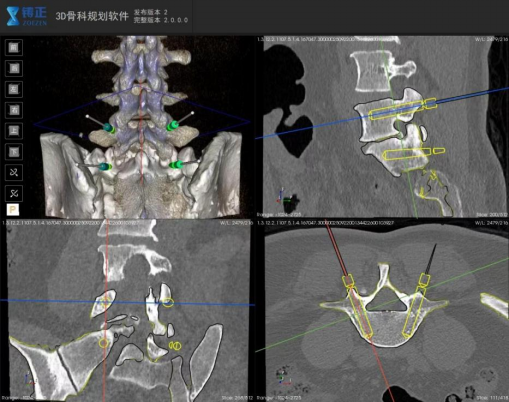

手术机器人辅助下的术前规划置钉路径

作为此次手术的“核心导航系统”,铸正佐航301手术机器人从根本上突破了传统手术的精度局限。术前,团队通过机器人影像分析模块对患者腰椎CT和MRI数据进行三维重建,精准还原腰5-骶1节段的解剖结构,智能规划出更优穿刺路径与置钉角度,有效规避了神经血管密集区域。